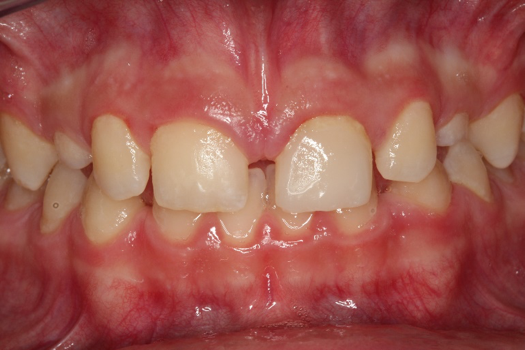

Fig 8. Photograph, 14-year-old brother.

Figure 8

Figure 5 through Figure 12 exemplify what currently may present in private dental practices with these types of patients. Four brothers aged 14 years to 27 years all suffered from obstructed airways; high incidence of caries of dentin, enamel, and cementum; moderate periodontal disease; collapsed vertical; undiagnosed OSA; and the potential for increase in comorbidities such as diabetes, cardiovascular disease, dementia, cancer, high blood pressure, and others. Symptomology was presented throughout the young lives of the brothers in this family. The parents were unaware that the dental agenesis and premature permanent tooth extraction could have led their sons into severe health issues as they matured.

Swift intervention took place with caries control, periodontal care, orthodontic evaluation for arch form development to aid in the development of facial bones and creating an improved upper airway with nasal patency. These interventions were followed up with definitive implant therapies and rapidly advancing restorative technology and materials. Thus, not only were these young men's smiles restored, they also were provided with the opportunity to regain their dignity when they become confident with their new smiles.